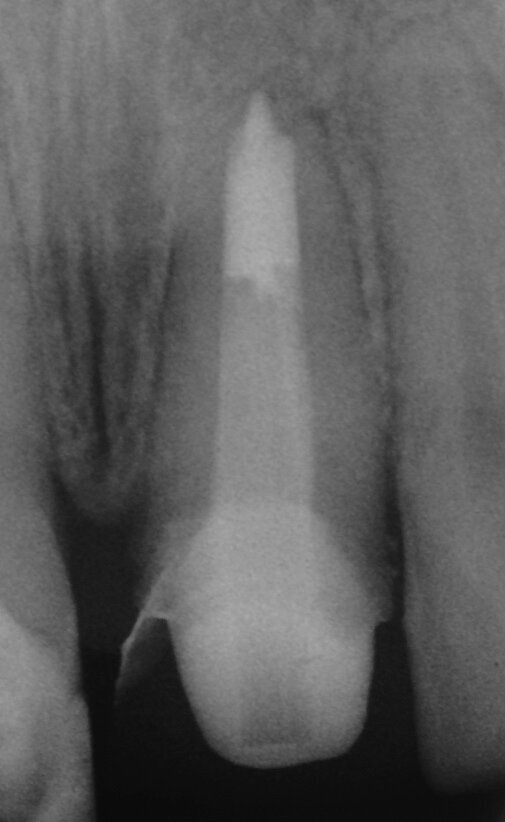

Fig. 3a: (a) Radiolucency in the cervical part of the canine. (b) Bleeding from the perforation. (c) MTA application with the MAP System and PD MTA White. (d) Original canal and repair of root perforation. (e) Post-op radiograph showing the root canal filling.

Fig. 3b: (a) Radiolucency in the cervical part of the canine. (b) Bleeding from the perforation. (c) MTA application with the MAP System and PD MTA White. (d) Original canal and repair of root perforation. (e) Post-op radiograph showing the root canal filling.

Fig. 3c: (a) Radiolucency in the cervical part of the canine. (b) Bleeding from the perforation. (c) MTA application with the MAP System and PD MTA White. (d) Original canal and repair of root perforation. (e) Post-op radiograph showing the root canal filling.

Fig. 3d: (a) Radiolucency in the cervical part of the canine. (b) Bleeding from the perforation. (c) MTA application with the MAP System and PD MTA White. (d) Original canal and repair of root perforation. (e) Post-op radiograph showing the root canal filling.

Fig. 3e: (a) Radiolucency in the cervical part of the canine. (b) Bleeding from the perforation. (c) MTA application with the MAP System and PD MTA White. (d) Original canal and repair of root perforation. (e) Post-op radiograph showing the root canal filling.

Repair of root perforations

Accidental perforation of the pulp chamber or of the root canal significantly changes the prognosis of the tooth. Perforation repair with a biocompatible sealing material such as MTA may save compromised teeth (Figs. 3a–e).[5]